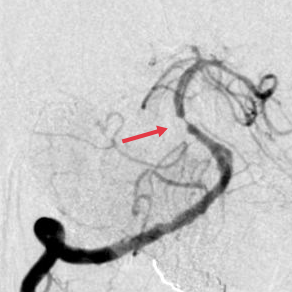

行基底动脉球囊扩张术+基底动脉支架植入术后,基底动脉开通。

12:26分:急性脑梗死、基底动脉闭塞诊断明确后,卒中介入小组急诊完成全脑血管造影术+右侧椎动脉取栓术+基底动脉球囊扩张术+基底动脉支架植入术。全程进展顺利,入院到基底动脉再通时间为73分钟。